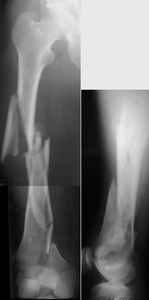

Attached are few examples from our Hospital:

A. Difficult reductions, even in retrograde nailing (my preference, easier control of "small" distal fragment) and it is much, much harder to do it anterograde (Alex, do you have one good case in your collection of anterograde nailing in very distal fractures - as you have suggested that I

should have done it in my previously posted case?

Malpositioning is much too common (recurvatum, varus - valgus).

B. Fixation loosening: distal cutting of the nail, non-unions do happen (cases attached).